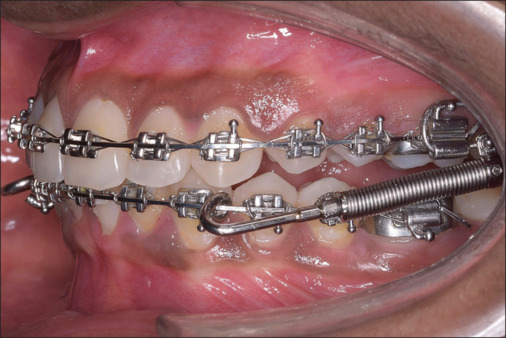

Methodology: A retrospective analysis was undertaken using the pre- and post-treatment records of 35 skeletal class II patients who used the FFRD to achieve class II correction. The metrics suggested by Solow and Rocabado were used to evaluate the cranial and cervical positions. Eleven angular parameters were evaluated to determine the relationship between the mandibular ramus and the skull as well as the upper and middle craniocervical positions. To compare the parameters before and after fixed functional therapy, a Wilcoxon signed rank test was used.